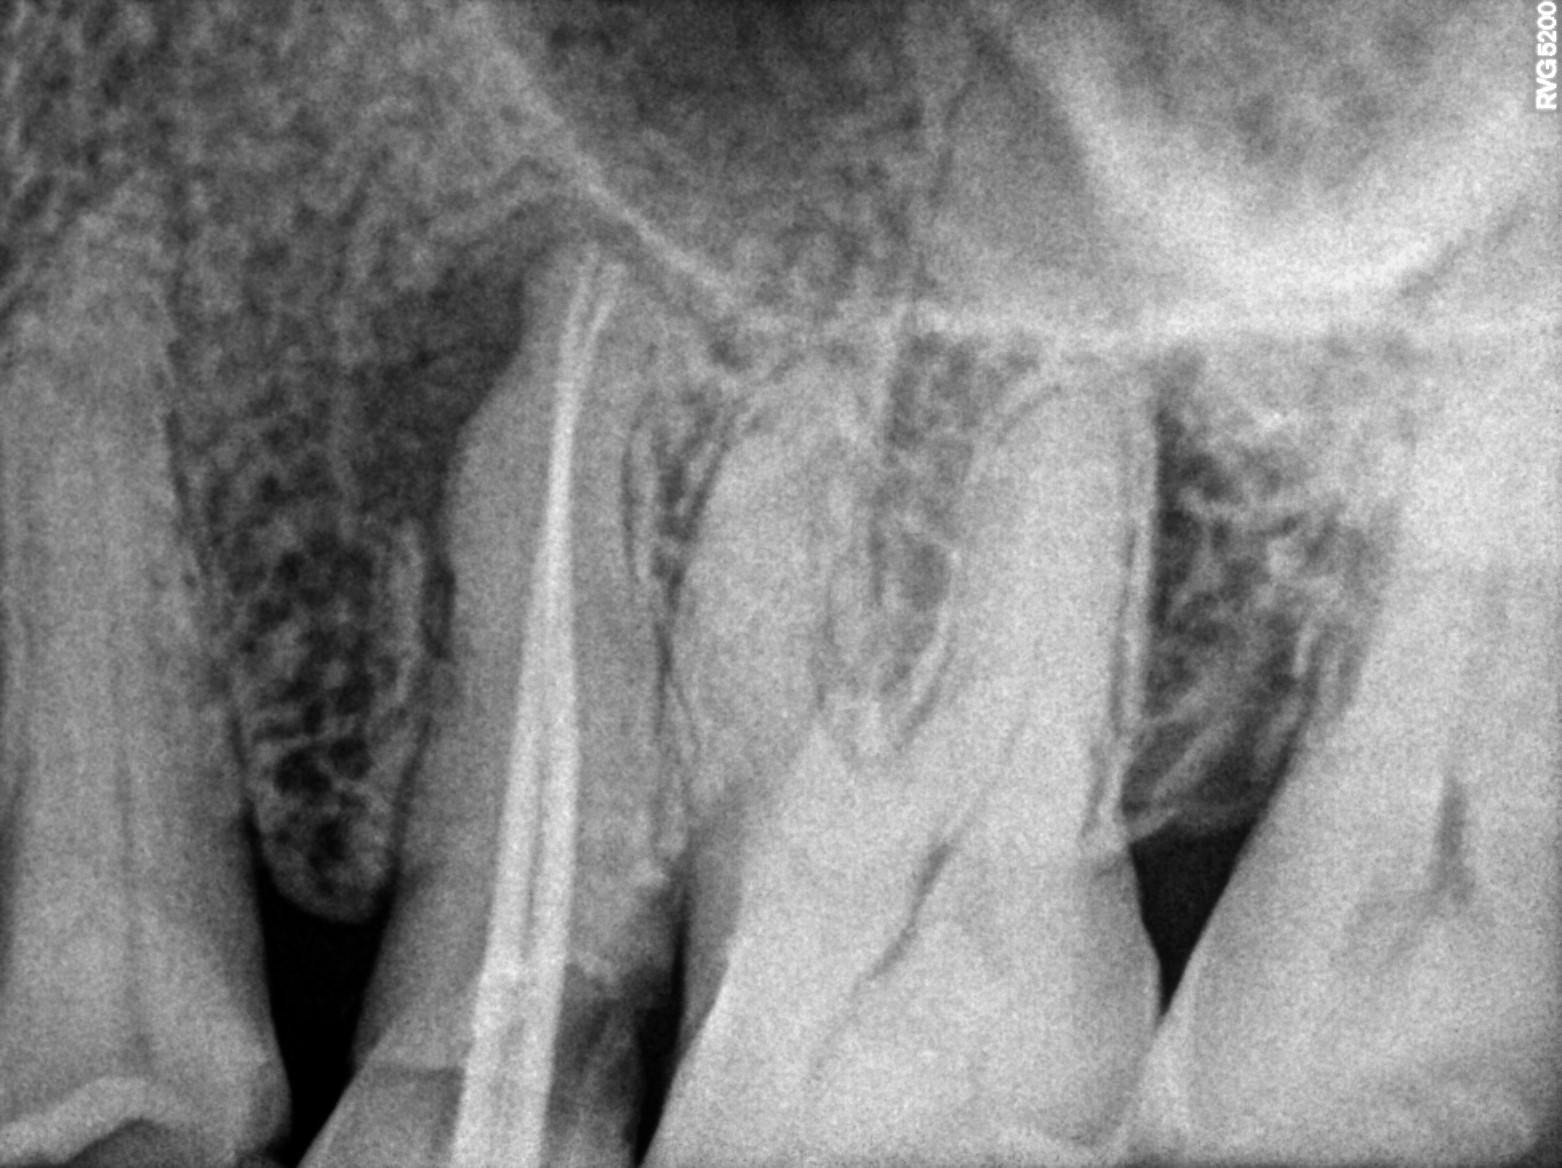

Dental Radiographs FHIR: DocumentReference · LOINC 24641-7

R59.jpg

24641-7